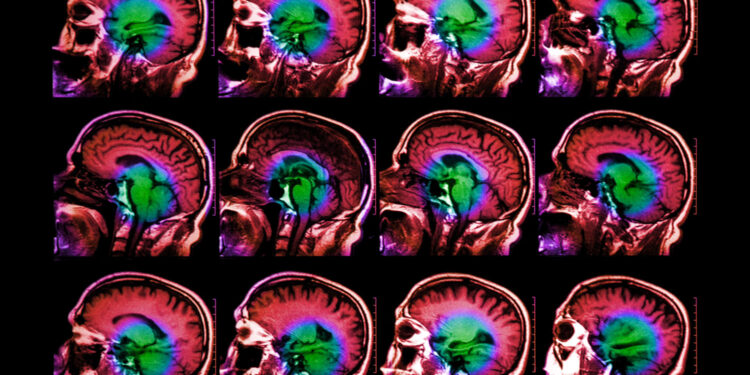

Using functional magnetic resonance imaging (fMRI), neuroscientists have identified several regions of the brain that are responsible for processing language. However, discovering the specific functions of neurons in those regions has proven difficult because fMRI, which measures changes in blood flow, doesn’t have high enough resolution to reveal what small populations of neurons are doing.

Functional MRI, which has helped scientists learn a great deal about the roles of different parts of the brain, works by measuring changes in blood flow in the brain. These measurements act as a proxy of neural activity during a particular task. However, each “voxel,” or three-dimensional chunk, of an fMRI image represents hundreds of thousands to millions of neurons and sums up activity across about two seconds, so it can’t reveal fine-grained detail about what those neurons are doing.